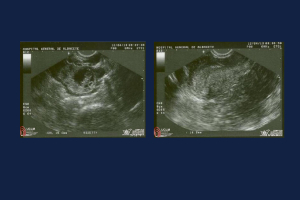

En el marco de su formación académica, estudiantes del 4° Módulo de la Licenciatura en Médico Cirujano de la Facultad de Medicina Humana “Dr. Manuel Velasco Suárez”, Campus II de la Benemérita Universidad Autónoma de Chiapas (UNACH), presentaron un reporte de caso clínico titulado “Embarazo Ectópico Derecho No Roto: Reporte de un Caso en el Hospital Vida Mejor del ISSTECH”, destacando la importancia del diagnóstico temprano y el manejo conservador en esta urgencia gineco-obstétrica.

El estudio, elaborado por Corzo de Coss, Grettel, Aguilar Trejo, Montserrat, Zúñiga González, Gabriela,  Martínez Gordillo, Angelica, Rosales Vidal, Ángel y Esquinca Ruiz, José Daniel, describe el caso de una paciente femenina de 32 años con diagnóstico de embarazo ectópico tubárico derecho no roto, tratado exitosamente con metotrexato, preservando la fertilidad y evitando complicaciones quirúrgicas.

En el caso reportado, la paciente presentó dolor abdominal bajo y sangrado vaginal leve, con amenorrea de siete semanas. Los estudios de laboratorio mostraron β-hCG sérica de 4,200 mUI/mL y hemoglobina de 10.2 g/dL, mientras que el ultrasonido transvaginal evidenció útero vacío y un saco gestacional en el anexo derecho. Dado su estado hemodinámicamente estable, se optó por manejo médico con metotrexato, con evolución favorable.

El diagnóstico temprano mediante ultrasonido transvaginal y medición sérica de β-hCG ha permitido tratamientos menos invasivos, como el manejo médico con metotrexato, que favorecen la preservación de la fertilidad. Este caso ejemplifica la eficacia de tales enfoques en pacientes seleccionadas.